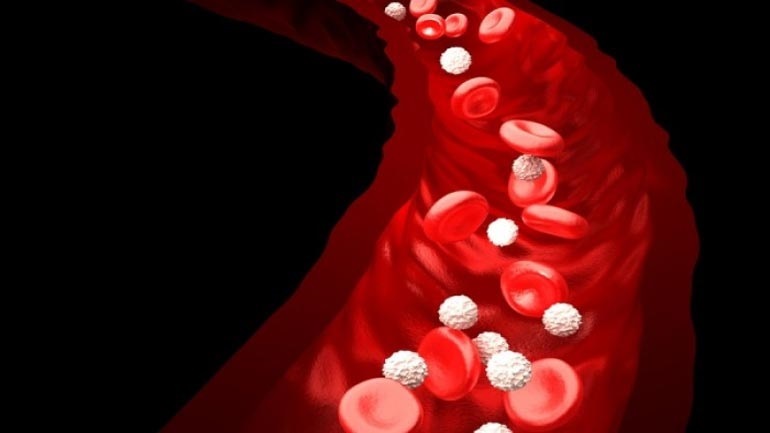

Κινήσου ενάντια στη θρόμβωση

Το μήνυμα «Κινήσου ενάντια στη θρόμβωση» ήταν το κεντρικό μήνυμα όλων των ομιλητών κατά τη διάρκεια Συνέντευξης Τύπου που οργάνωσε το Ι.Μ.Ε.Θ.Α., με αφορμή τον εορτασμό της Παγκόσμιας Ημέρας Θρόμβωσης (13 Οκτωβρίου). Ο εορτασμός της Παγκόσμιας Ημέρας Θρόμβωσης που φέτος κλείνει τα 10 χρόνια, έχει την επιστημονική αρωγή 19 Επιστημονικών Εταιρειών που σχετίζονται με τη […]